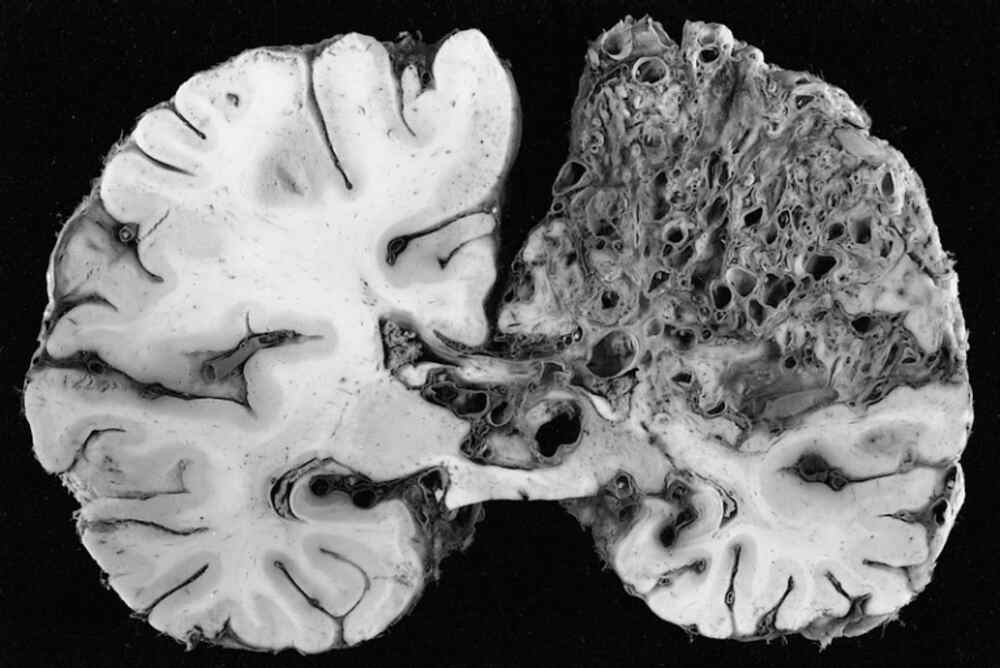

A brain Arteriovenous Malformation (AVM) is an uncommon abnormal cerebral blood vessels. It interferes with normal blood flow through direct connections between veins and arteries that bypass the vital capillary system. This condition causes high-pressure blood flow in weak vessels, which are more prone to rupture. If untreated, the AVMs in the brain pose serious risk to health as the weak vessels can rupture in a way that could cause bleeding within the brain (hemorrhage) or stroke or irreparable neurological damage. Early diagnosis and treatment in a specialist AVM hospital such as IRFacilities are vital to prevent these serious problems and maintaining the neurological function.

There is no evidence of cause of this condition that is not a result of environmental or lifestyle factors. Thus, the diagnosis is crucial and heavily depends on the area that is AVM Radiology. Modern imaging techniques such as MRI as well as CT angiography are employed to precisely determine the size of the malformation and location as well as pattern of flow. The precise radiological assessment is vital for precise guidance in subsequent treatment plans and to ensure a safe treatment strategy.